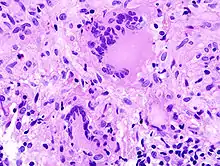

- Histologisch: Nekrosen, Kapillarisierung (Neoangiogenese), Aufhebung der normalen Histologie.

- Zytologisch: Polymorphie, basophiles Cytoplasma, erhöhte Kern/Plasmarelation

- Nukleär: Polymorphie, Polychromasie, Hyperchromasie, Aneuploidie, (vergrößerte) Nukleolen, vermehrt Mitosen, atypische Mitosen, erhöhter Proliferationsindex (Ki-67 = MIB-1).